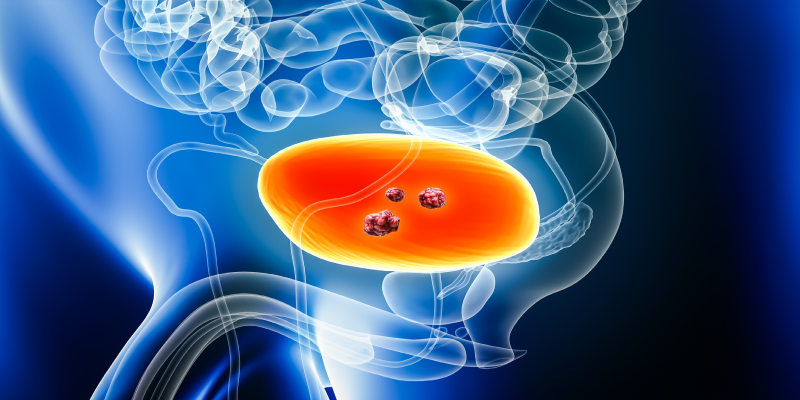

pT2 Mesane Kanseri

Mesane kanseri, genellikle T evreleme sistemi (T: tümörün büyüklüğü ve mesanedeki yayılımı) kullanılarak evrelenir. “T” harfi, kanserin mesaneye ne kadar yayıldığını belirtir. pT2, kanserin mesanenin kas tabakasına (müsküler tabaka) yaydığını ifade eder.

pT2 mesane kanseri, kanserin mesanenin kas tabakasına (müsküleris propria) kadar ilerlediği anlamına gelir, ancak henüz mesanenin dışındaki organlara yayılmamıştır. Bu aşama, kanserin mesanenin daha derin tabakalarına, ancak dış organlara ya da vücudun diğer bölgelerine yayılmadığı bir evredir.